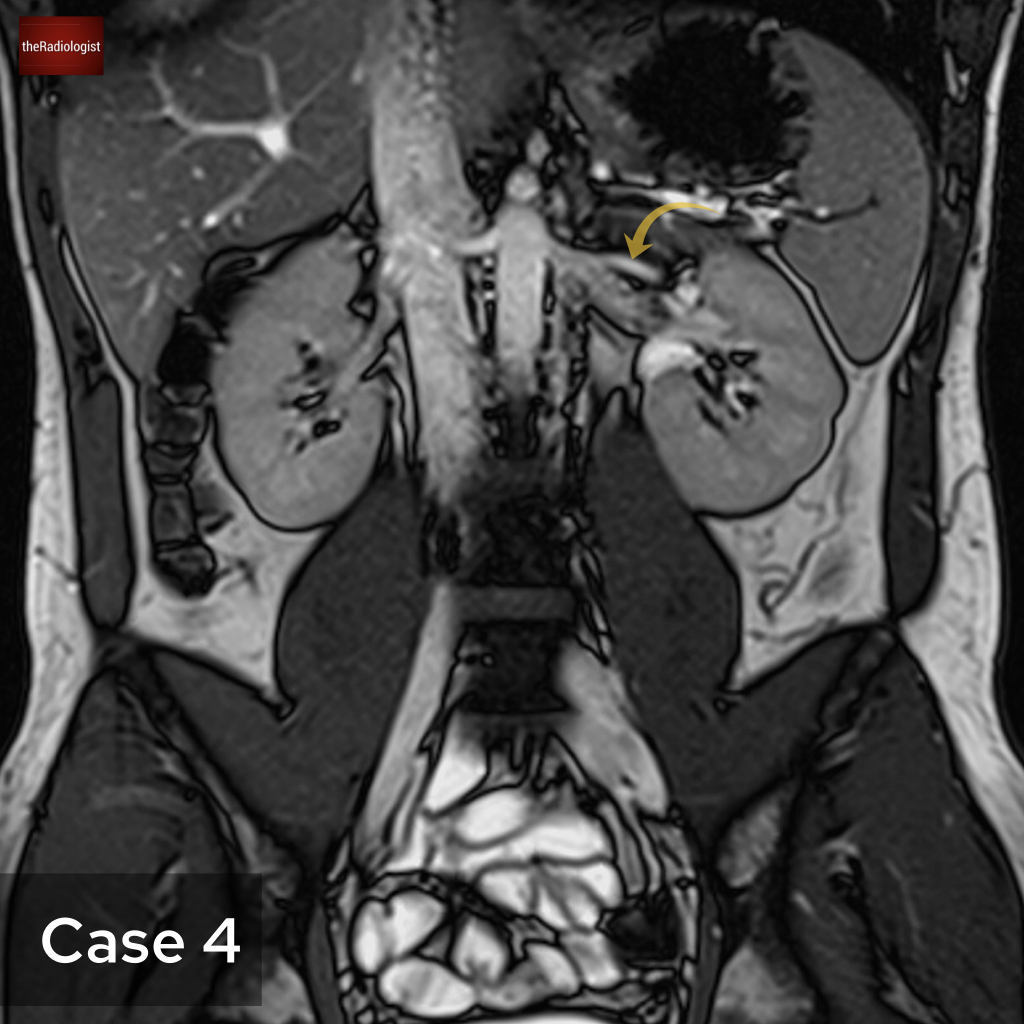

Case 4

Another abdominal MRI in this case. What is the arrow pointing at?

Choose one from the following options: